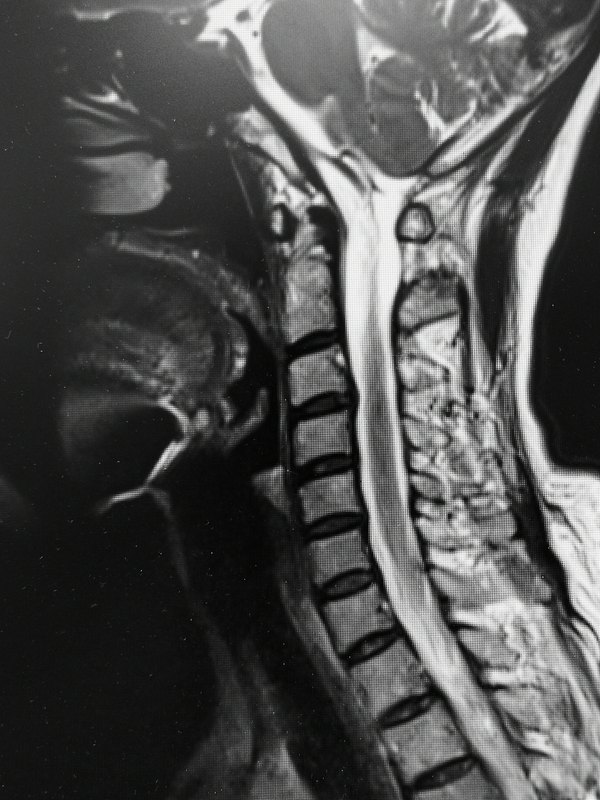

收獲良效 文/種濤 一位六十多歲患者,頸部不適伴雙上肢麻木,左眼疼痛干澀流淚,入睡困難等困擾一年余,經(jīng)同仁等眼科專科醫(yī)院診查治療多次,未發(fā)現(xiàn)器質(zhì)異常,未見好轉(zhuǎn)。 經(jīng)同事介紹周一來診,針刺治療一次,今天復(fù)診言所有癥狀均有明顯好轉(zhuǎn)。左眼不痛了,干澀流淚減輕,比右眼的感覺還好;近兩天沒有吃思諾思,但入睡比原來還容易,雙手麻木也緩解。患者的精氣神明顯好轉(zhuǎn),預(yù)約再來治療幾次,喜悅心情溢于言表。 頸椎損害除了常見的頸痛手麻頭暈等常見癥狀,也會導(dǎo)致頭痛失眠眼花惡心心慌易怒等交感神經(jīng)激惹癥狀。 中醫(yī)的優(yōu)勢就是在功能失常,還未出現(xiàn)品質(zhì)性損害時(shí)入手,每每收獲良效。